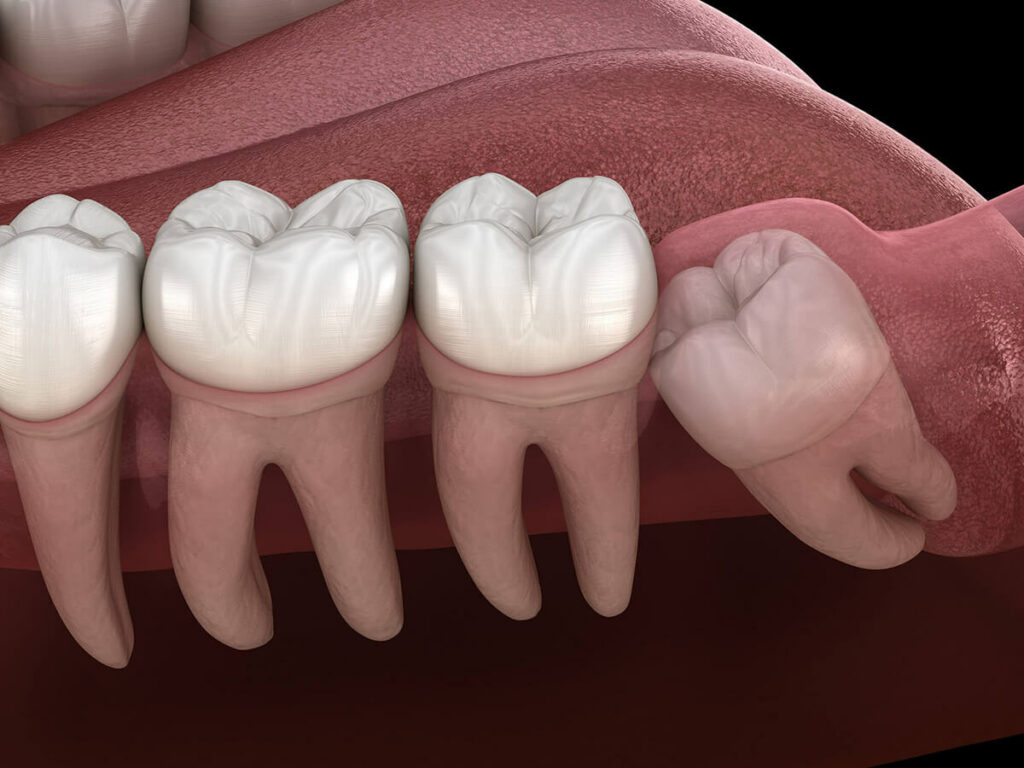

- Impaction, i.e., if the tooth is stuck under the gums or is completely hidden. If wisdom teeth aren’t able to emerge normally, they can become trapped within your jaw which can result in infection or cause a cyst that can damage other teeth or roots.

- Changing bite alignment—wisdom teeth can grow at various angles in the jaw, sometimes horizontally, this can cause a change in your bite alignment.

What is an impacted wisdom tooth?

When a wisdom tooth doesn’t have enough room to come in normally, it is considered an impacted wisdom tooth. There are several degrees of impacted wisdom teeth depending on where the teeth lie within the jaw. Soft tissue impaction occurs when the crown of the tooth has penetrated through the bone, but the gum is still covering part of the tooth. When the tooth has partially erupted, but a part of the tooth remains submerged in the jawbone, this is considered partially bony impaction. Complete bony impaction occurs when the tooth is entirely encased by jawbone.